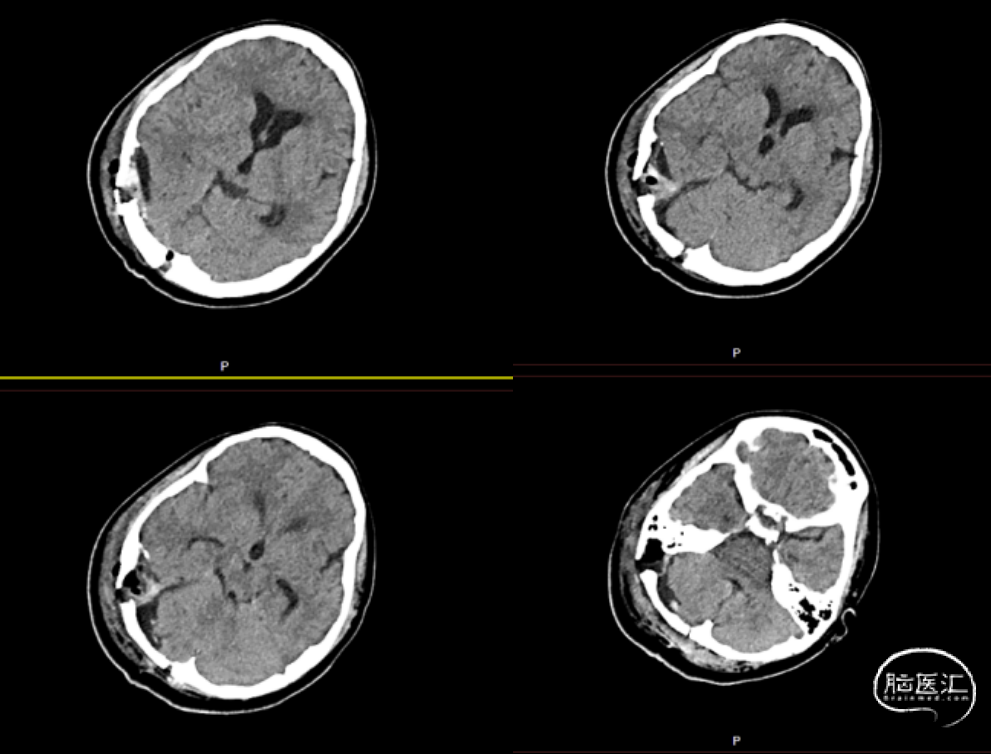

患者入院完善术前检查,头颅CT提示:右侧小脑半球-枕叶混杂密度肿块,大小约71*37mm,内见钙化,邻近颅骨骨质破坏、变薄,第四脑室受压(图1、图2)。进一步完善头颅增强MRI提示右侧颞枕部占位,脑外起源考虑,软骨肉瘤可能,血管瘤型脑膜瘤或血管瘤待排(图3)。

图3. 头颅增强MRI图像,见右侧颞枕部混杂长T1长T2信号肿块,大小约60*37mm,T1WI为低信号影,T2WI为高信号影,内见线样低信号影,增强后病变不均匀渐进性强化,临近脑实质及脑室系统受压,侧脑室和三脑室扩张积水。